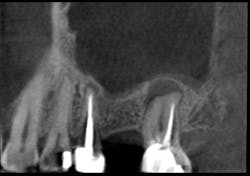

These alveolar bone changes often compromise implant placement due to thin bone volume (figures 2a–2d).

• Rebuild defects around adjacent teeth after extracting teeth due to periodontal disease (figures 5a–5c)